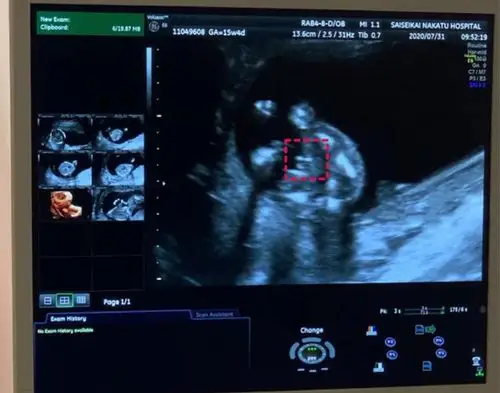

nt单子男宝三个亮点图